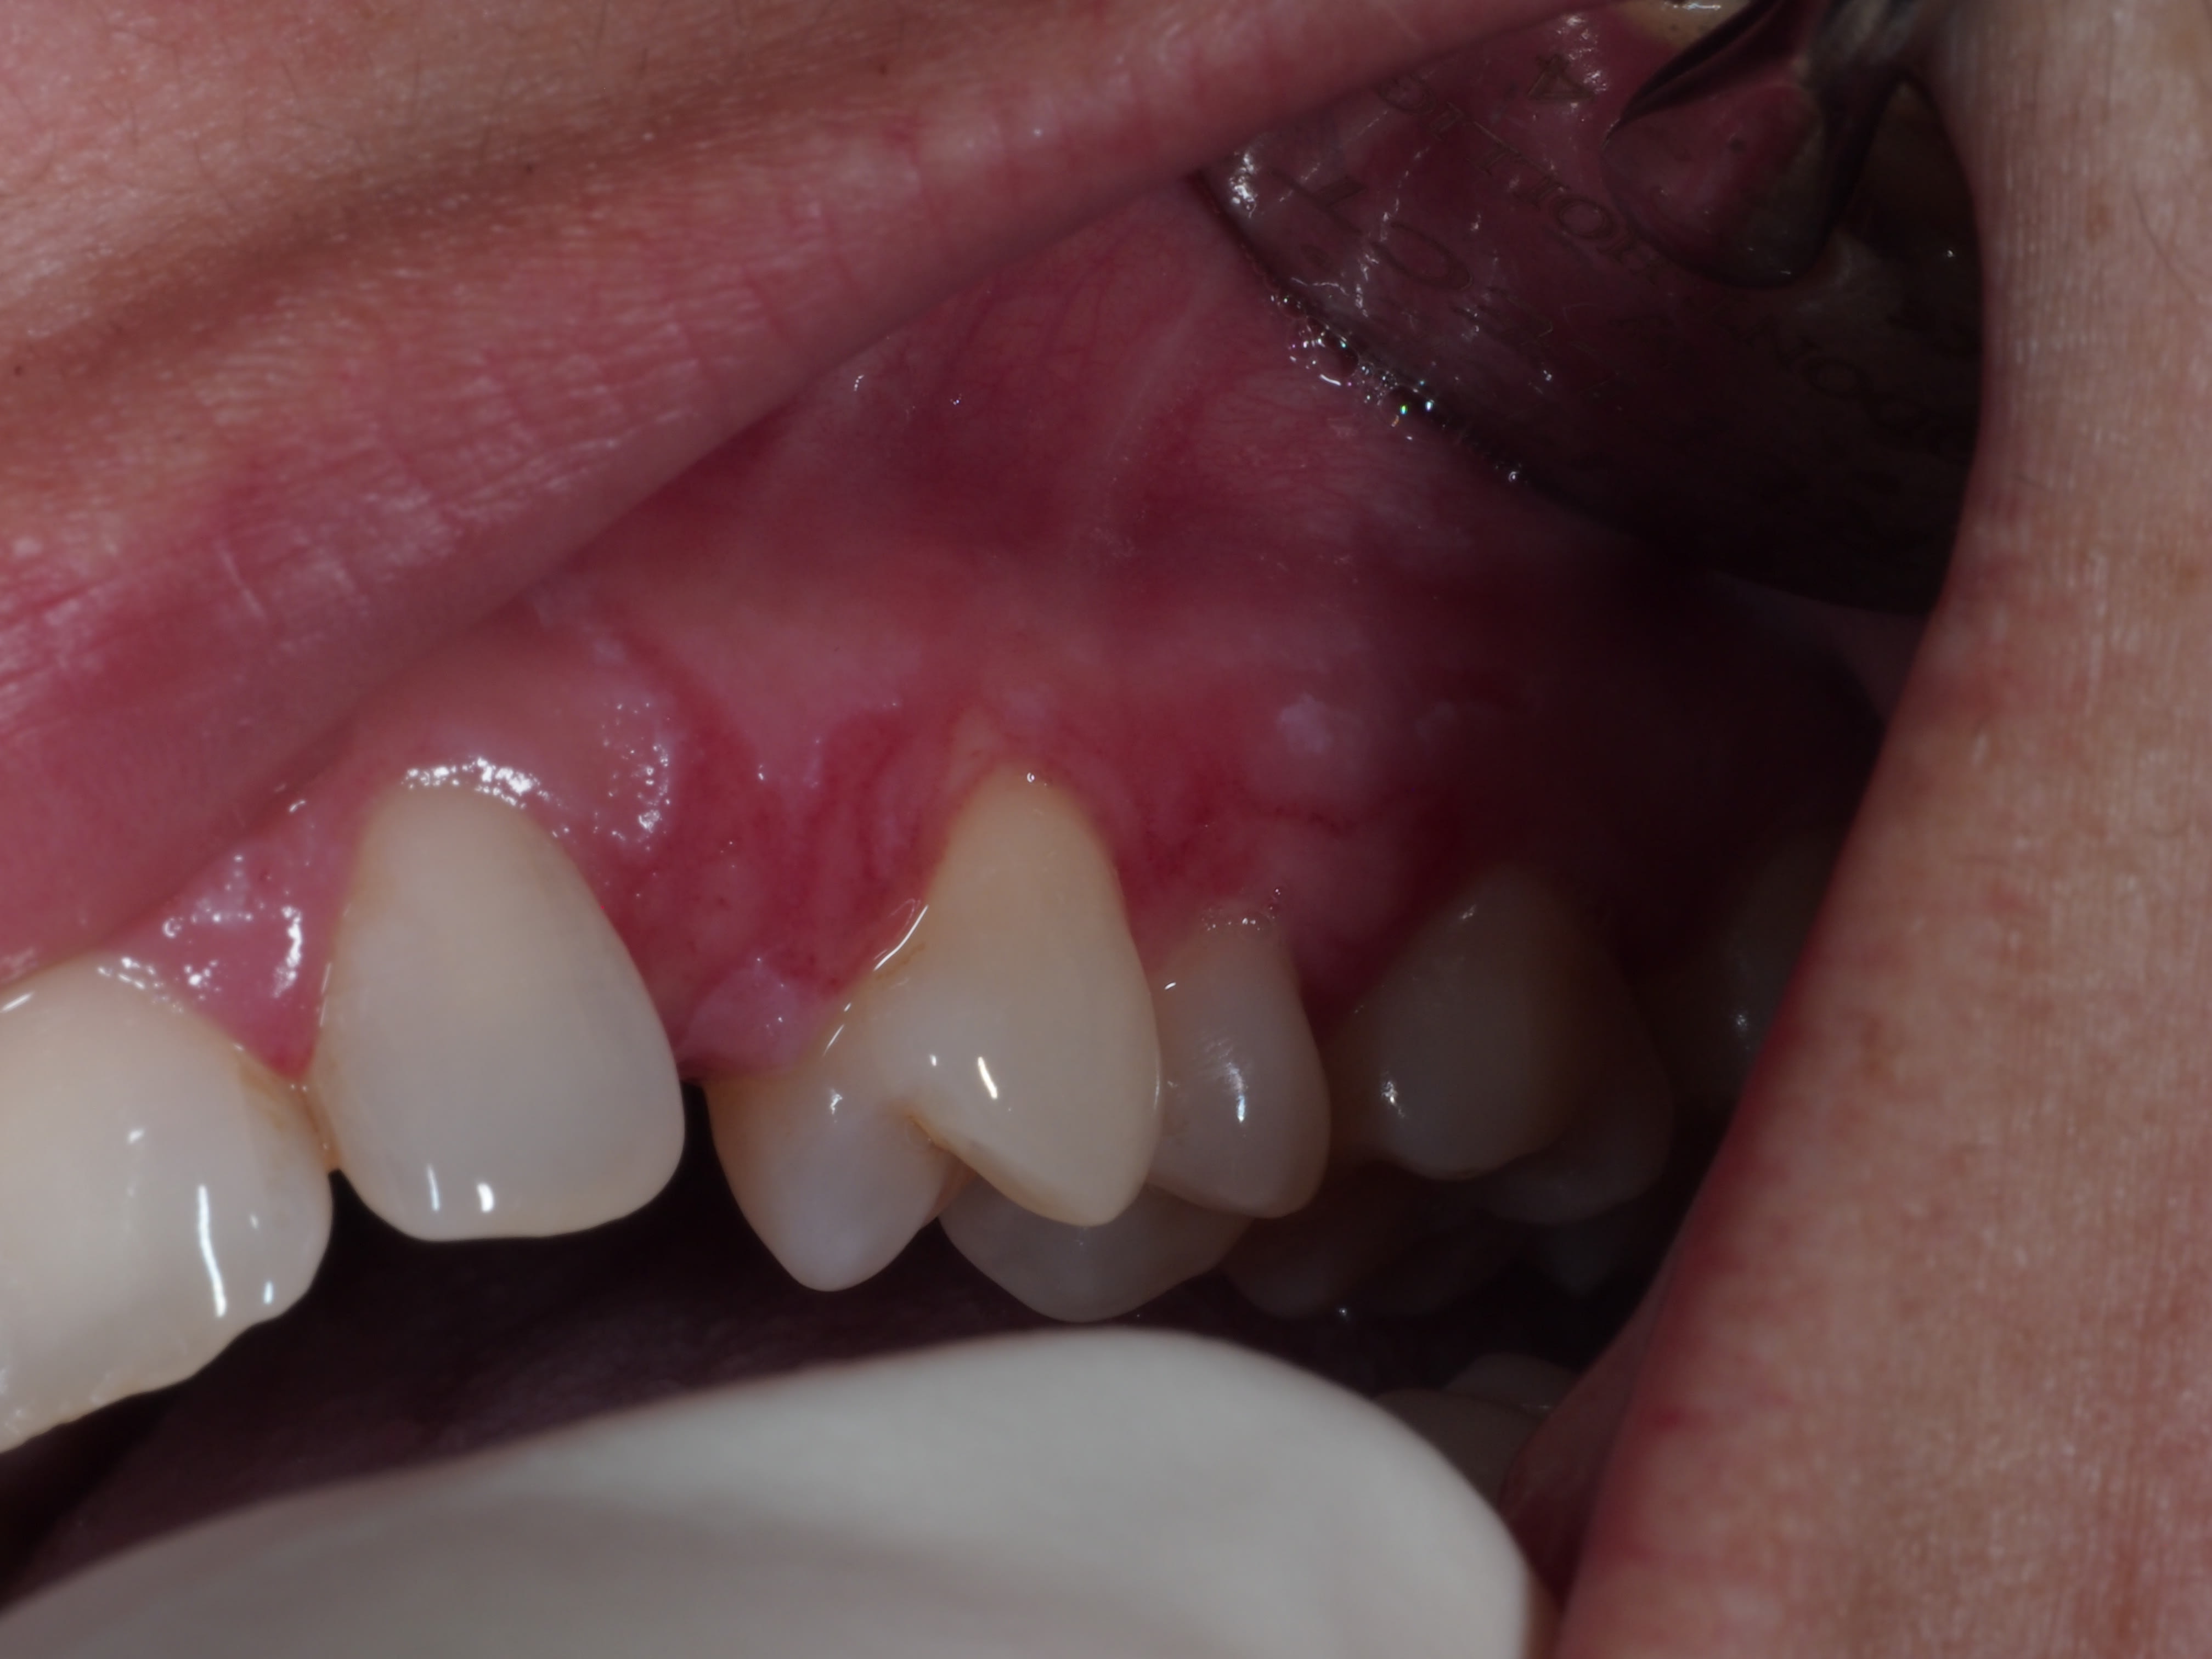

Bonjour, j'aurais besoin d'un petit coup de main, patiente venu en urgence ce jour avec lésion gingival (cf photo) et ganglion sous mandibulaire gauche +++. Canine incluse sous muqueuse.

Cet épisode antérieur me fait penser à une primo infection herpétique et cette lésion à une récidive. Mais je ne reconnais pas de vésicule sur la muqueuse gingivale , simplement 2/3 petites vésicules coté palatin / pas de photos :-(

Est ce que cette photos vous évoques une éthiologie virale ou est ce que vous pensez à autre chose ?

Y a t'il un rapport avec cette 23 ?

y aurait pas une ouverture du sac coronaire de la 23 dans la cavité buccale?